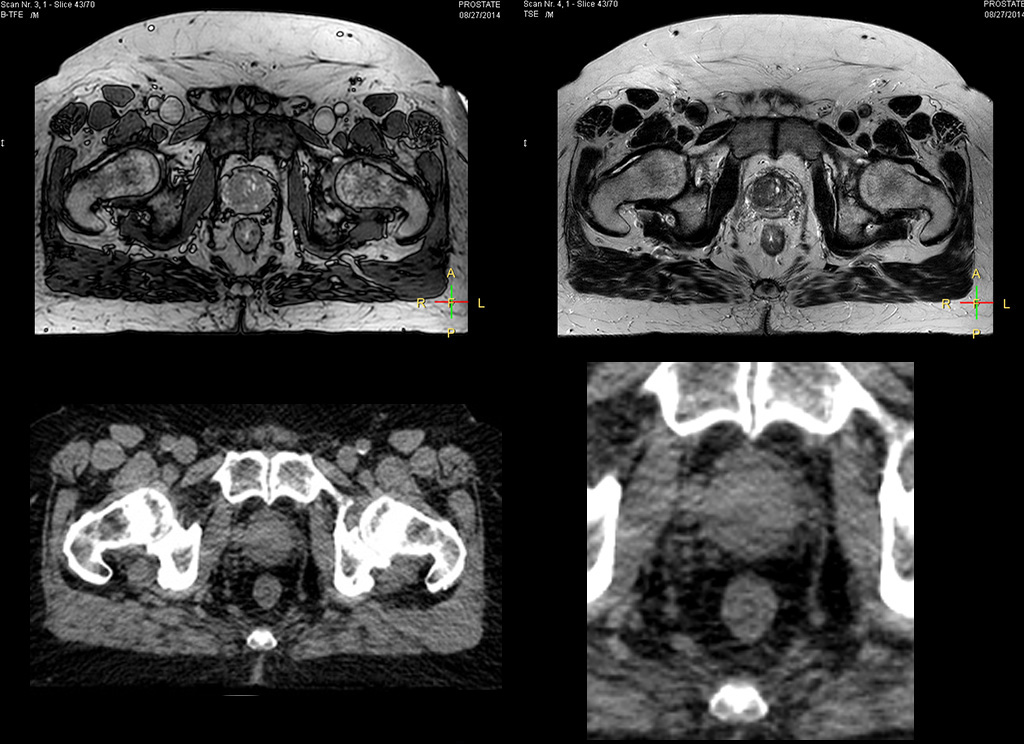

Impressive clinical benefits for prostate

“The biggest problem for CT-based planning, especially in prostate, is you can’t see the cancer very well,” says Dr. Stevens. “On CT it can be quite challenging to see the edge of the prostate especially at the apex. When the edge of the prostate can’t be delineated well on CT, radiation oncologists will increase their margins a little bit so they don’t miss it, but that can also increase toxicity.”

“Using MR, the prostate is well delineated. We quickly see the edges of cancerous tumors like in prostate cancer, and as normal structures can be defined, we can optimize the treatment plan to protect these organs and their normal function. This can potentially improve the outcome. And it improves workflow as well. We can contour more quickly, confident that the tumor is going to be in the field.”

“The Ingenia 3.0T MR scanner provides high resolution allowing us to make scans fast for the patients. It also gives the potential to include methods like MR spectroscopy and diffusion weighted Imaging, which we’re in the process of doing right now,” Dr. Stevens adds.

“When a patient registers, first CT simulation and MR simulation are done, followed by CT-MR registration on Pinnacle3. Then the target and normal organ delineation is performed on MR images. Meanwhile we create a reference CT image for online treatment and localization correction. During the treatment phase we can perform additional MRI scans to visualize the anatomy changes and create an adaptive plan. This plan basically adapts the treatment plan to the changes.”